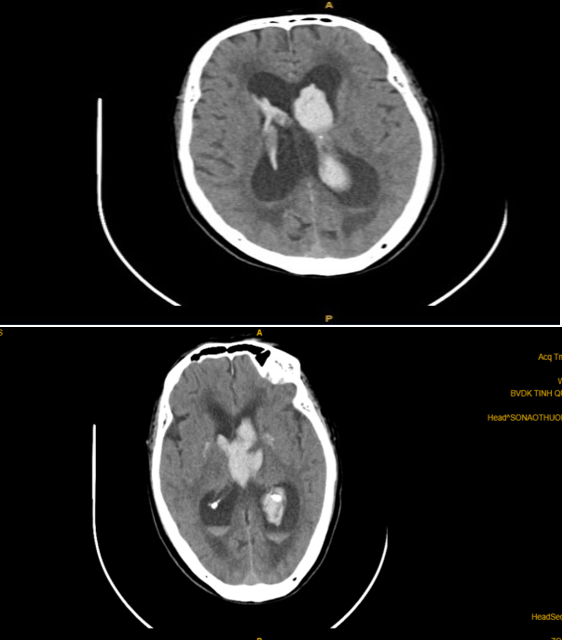

CT sọ não sau bơm 3 liều Alteplase